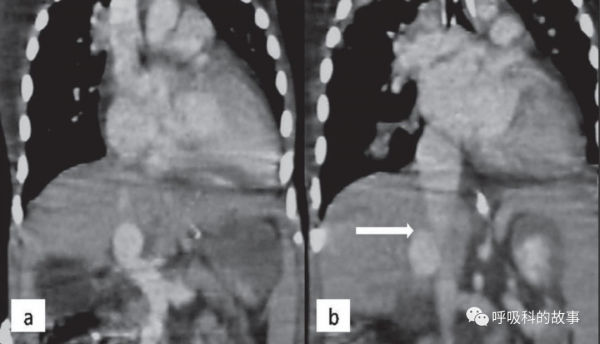

過了幾天全院針對本病進行討論,小楊首先彙報了後續的一些檢查,首先是腹部CT+門脈重建結果:

門靜脈及其肝內分支、脾靜脈未見顯示;腸繫膜靜脈經側支靜脈匯入左腎靜脈,下腔靜脈及其分支、雙腎靜脈增粗;胃左靜脈迂曲增粗,經胃周迂曲血管團,與左腎靜脈相通;食道下段,胃周,腹腔多發迂曲血管影;肝形態不規則,考慮肝硬化;肝內、雙腎多發囊腫;膽囊及脾臟未見明確顯示 。

間接門靜脈造影符合門脈高壓症。其次肝穿刺病理顯示“小條肝組織,大部分割槽域肝索排列擁擠,肝細胞腫脹,可見點狀壞死,肝細胞膽汁淤積,匯管區淋巴細胞浸潤。”

呂主任問道:“那這CT怎麼會未顯示門靜脈?”

楚院長說道:“這先天性門脈系統與腔靜脈系統分流畸形叫Abernethy綜合徵,是1793年英國外科醫生阿伯內西首先報道的。這種病門脈可缺如或者部分缺如,脾靜脈、腸繫膜靜脈直接匯入下腔靜脈,肝臟僅透過側支供血,可造成肝功能異常、門脈高壓、肝肺綜合徵、左心室擴大,可合併肝臟腫瘤或其他畸形。本病分兩型,I型門脈完全缺如,女性多見,根據脾靜脈和腸繫膜靜脈不匯合或匯合分為Ia和Ib型;II型為門脈部分缺如,脾靜脈透過側支分流與下腔靜脈溝通。對於造成肝功能異常和門脈高壓者,II型患者可考慮將門脈和下腔靜脈的側支分流結紮或栓塞,I型患者只能進行肝臟移植。”